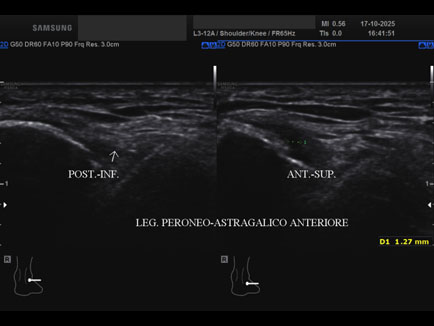

Ecografia del: 17/10/2025

Età Paziente: M

Commento all'esame: rottura del fascio antero-superiore del legamento fibulo-talare anteriore con integrità del fascio postero-inferiore in giovane calciatore.

Conclusioni: rottura del fascio antero-superiore del legamento fibulo-talare anteriore destro (tear of the anterosuperior bundle of the right anterior talofibular ligament).